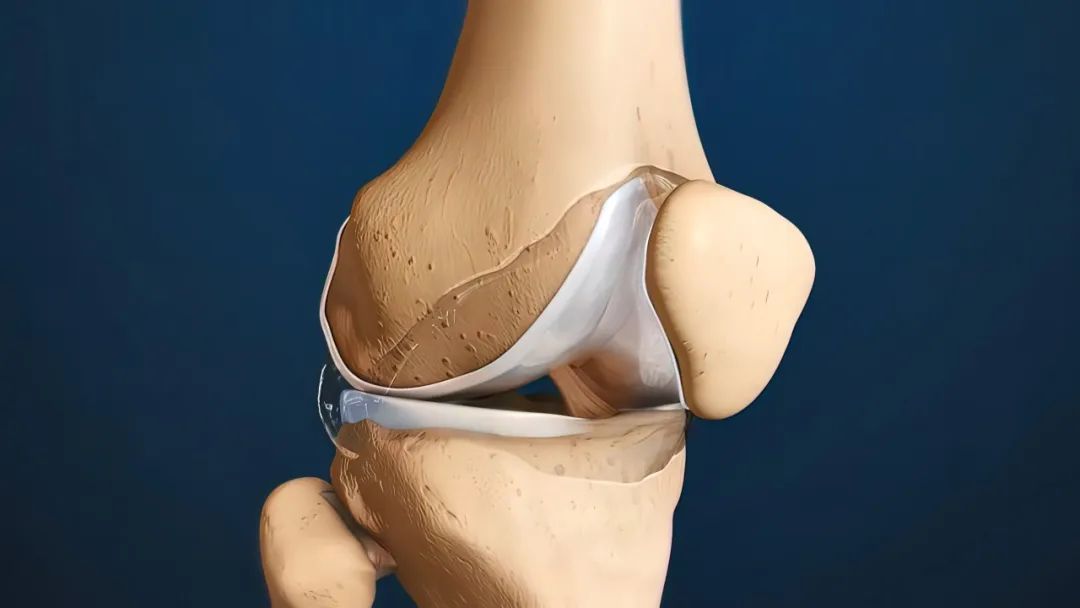

这就需要给大家补充一个知识点了,要想保护膝盖,不只是保护好上下两根梆硬的棒子骨就对了,膝盖软骨的健康也很重要。

软骨的作用非常关键,一方面,它可以充当骨头之间的“缓冲垫”,让骨头在应对压力和冲击的时候不至于被破坏。

另一方面,它也起到润滑关节的作用,我们平时伸腿弯腿那么丝滑,膝盖软骨功不可没。

但是,要想软骨干活出力,同时又要保持健康,营养供给就必须要跟上。

实不相瞒,主要靠你多多迈开腿,多让关节软骨活动活动。平时挤压软骨的过程,就可以把关节滑液中的营养送到细胞里面。